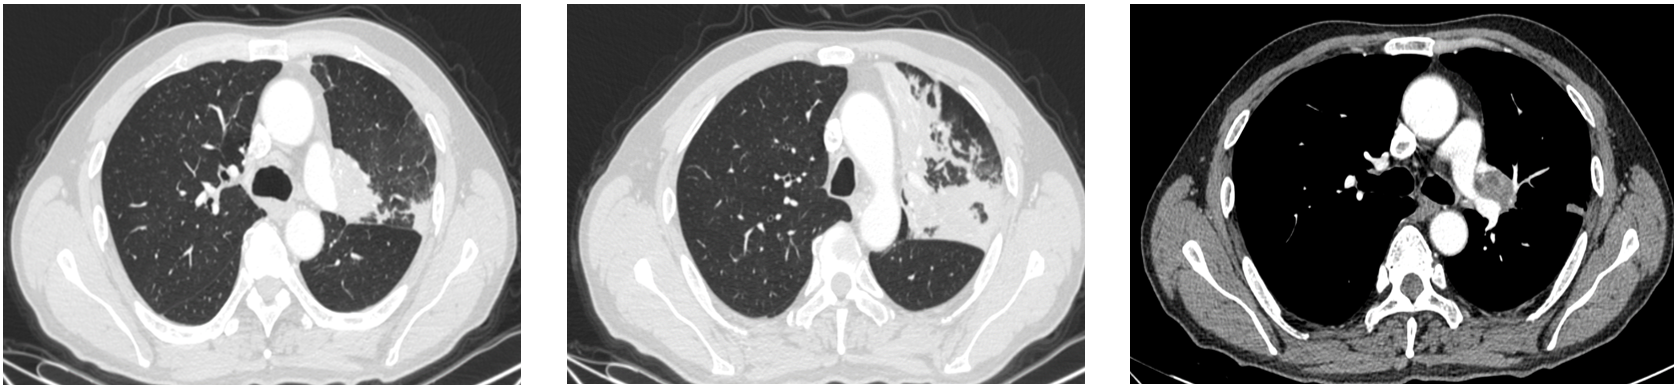

胸部CT(2021/11/03): 左肺占位,考虑恶性病变;左肺上叶炎性改变,左肺门淋巴结增大。

PET-CT(2021/11/10): 左肺上叶近肺门处占位(4.2x3.5cm),伴左肺上叶多发高密度影,FDG代谢增高;右肺中叶实性小结节,FDG代谢不高,考虑炎性结节可能;纵隔内(4L、8区)和左肺门淋巴结增大,FDG代谢增高。双侧胸膜局部增厚。

影像学评估: 治疗后复查胸部CT(2022/1/6)显示左肺门占位较前范围缩小(1.2x1cm),左肺门淋巴结缩小,炎性改变明显好转。疗效评估为部分缓解(PR)。